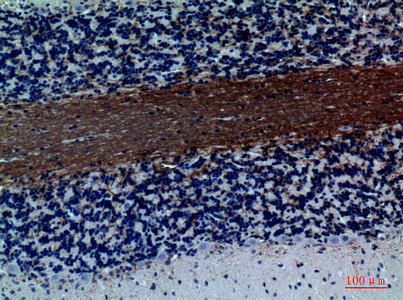

Application

| WB, IHC-P |

| Dilution | WB~~Western Blot: 1/500 - 1/2000. IHC-p: 1:100-1:300. ELISA: 1/10000. Not yet tested in other applications. IHC-P~~Western Blot: 1/500 - 1/2000. IHC-p: 1:100-1:300. ELISA: 1/10000. Not yet tested in other applications. |